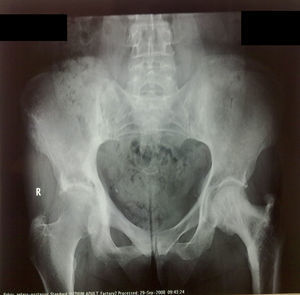

Se realizó radiología de columna cervical donde se apreció una rectificación de la lordosis fisiológica. La radiología de la columna lumbar evidenció un patrón escleroso en las articulaciones sacroiliacas (fig. 1).

Con la sospecha de enfermedad de Paget se solicitó una gammagrafía ósea con Tc-99 (fig. 2), en la que se apreció un aumento de captación en la vértebra D 10, tercera articulación interfalángica proximal izquierda, pelvis y fémur izquierdo. Se solicitó radiología simple de las regiones captantes, destacando la afectación de la tercera falange de la mano izquierda, siendo el resto de la imagen radiográfica normal (fig. 3).